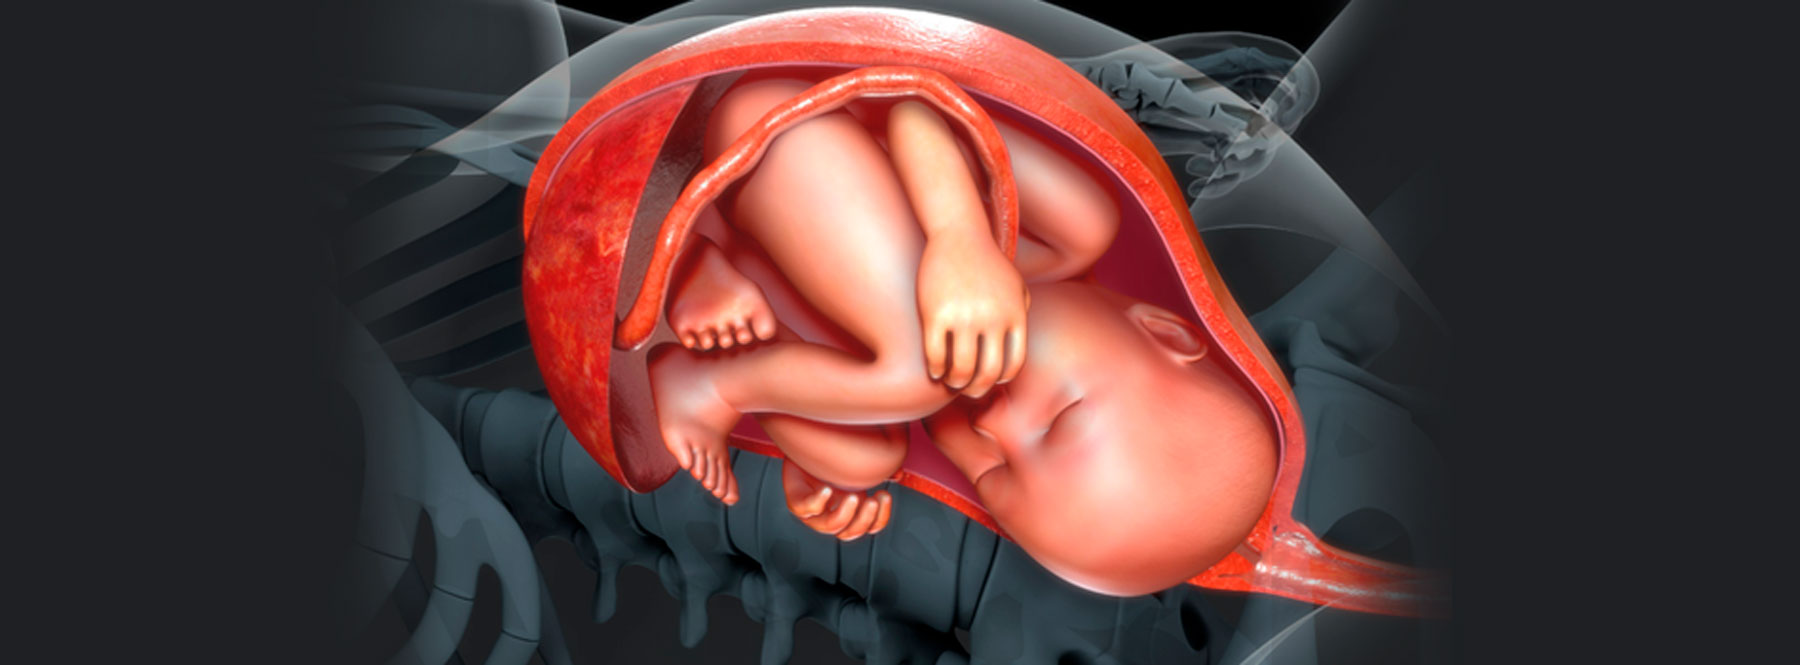

ESPECIALIZACIÓN EN Medicina Materno Fetal

La Especialización en Medicina Materno Fetal es un programa de segunda especialidad que se desarrolla en convenio con la Clínica Universitaria Colombia. El programa tiene como misión formar especialistas con una visión integral en la valoración clínica, diagnóstico, tratamiento y seguimiento de las gestantes en condición de alto riesgo, fomentando el desarrollo de la investigación, el aprendizaje y la docencia que contribuyan a mejorar la problemática de salud en el área y el desarrollo de políticas de salud, que impacten en la calidad de vida de las pacientes y sus familias.

¿Por qué estudiar la Especialización en Medicina Maternofetal?